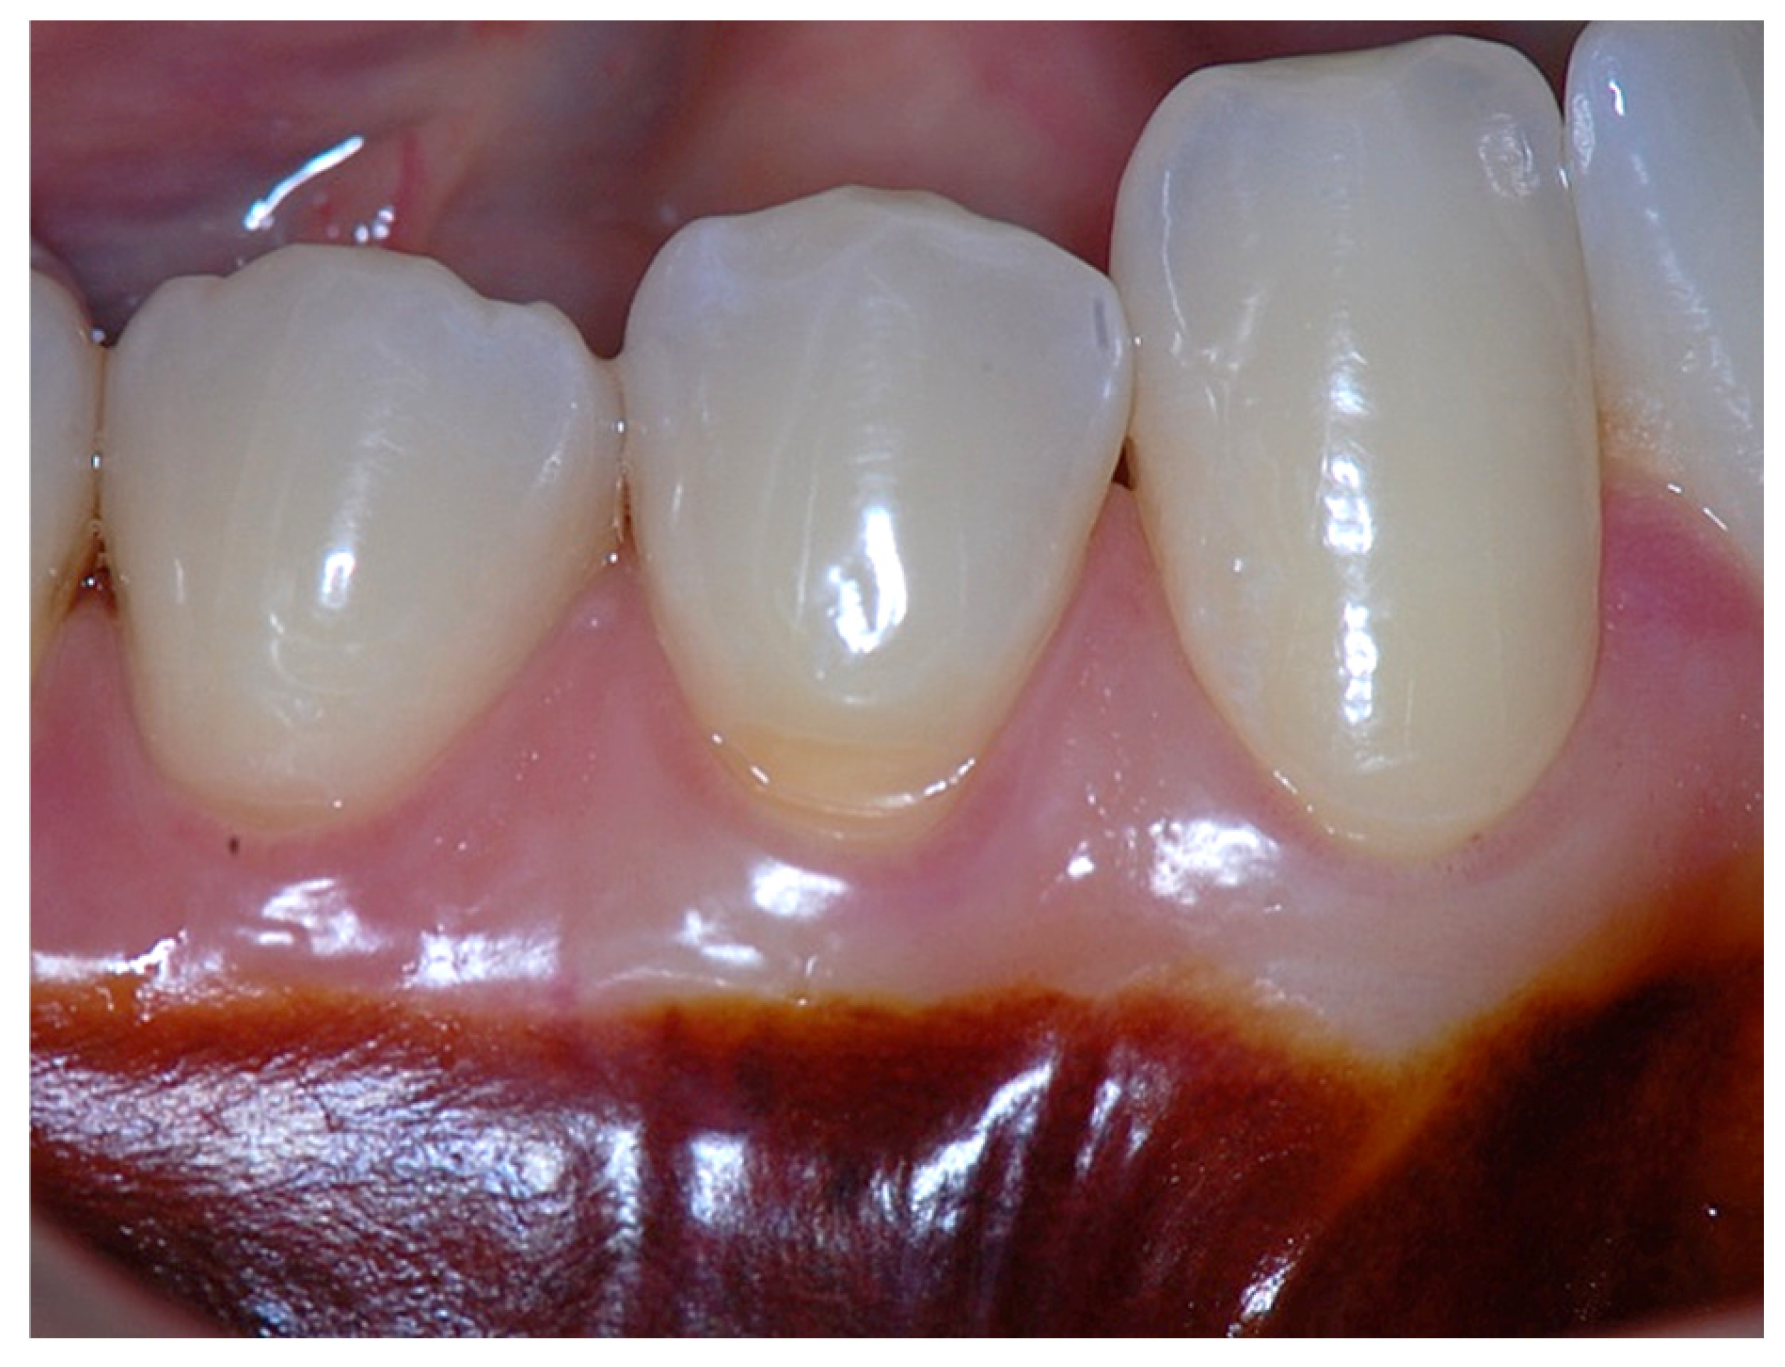

Figure 5. Probing depth of 1 mm associated with 1 mm of epithelial attachment, 1 mm of connective tissue fiber insertion into the root cementum, and connective tissue fibers inserting into the alveolar bone.

Clinically, an ideal scenario involves a keratinized tissue width of ≥3 mm, as this configuration supports connective tissue fiber insertion into both the root surface and the periosteum of the alveolar bone (Figure 7, Figure 8, Figure 9, Figure 10 and Figure 11). Notably, a KT width ≥3 mm represents the only condition that fully aligns with classical definitions of attached gingiva in the periodontal literature and with American Academy of Periodontology criteria, which describe AG as being firmly attached to the underlying alveolar bone and root cementum by dense connective tissue fibers [1,3,34,35].

Beyond SCTA dimensions, the orientation and insertion pattern of supracrestal connective tissue fibers relative to the keratinized tissue play a critical role in gingival margin stability, provided that anatomical landmarks remain within physiological limits, namely approximately 1 mm of epithelial attachment and 1 mm of probing depth (Figure 8, Figure 9, Figure 10 and Figure 11).